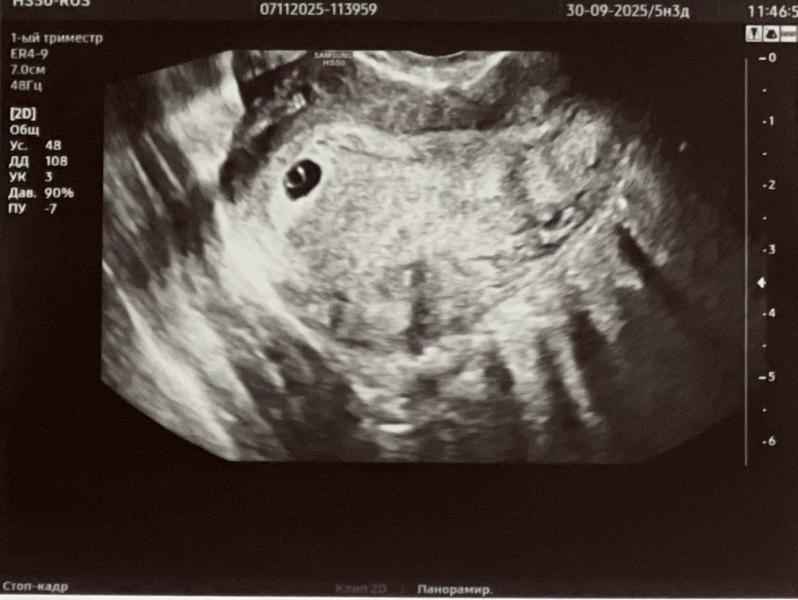

Моя тревожность не дала спокойно ждать узи в женской консультации .

Тк пришел Хгч от 5 ноября 5698, а днем ранее на узи ничего не увидели 🙈

И мазня какая-то появилась (

Сегодня на узи разглядели все , что положено по сроку 😍( 5.3 )